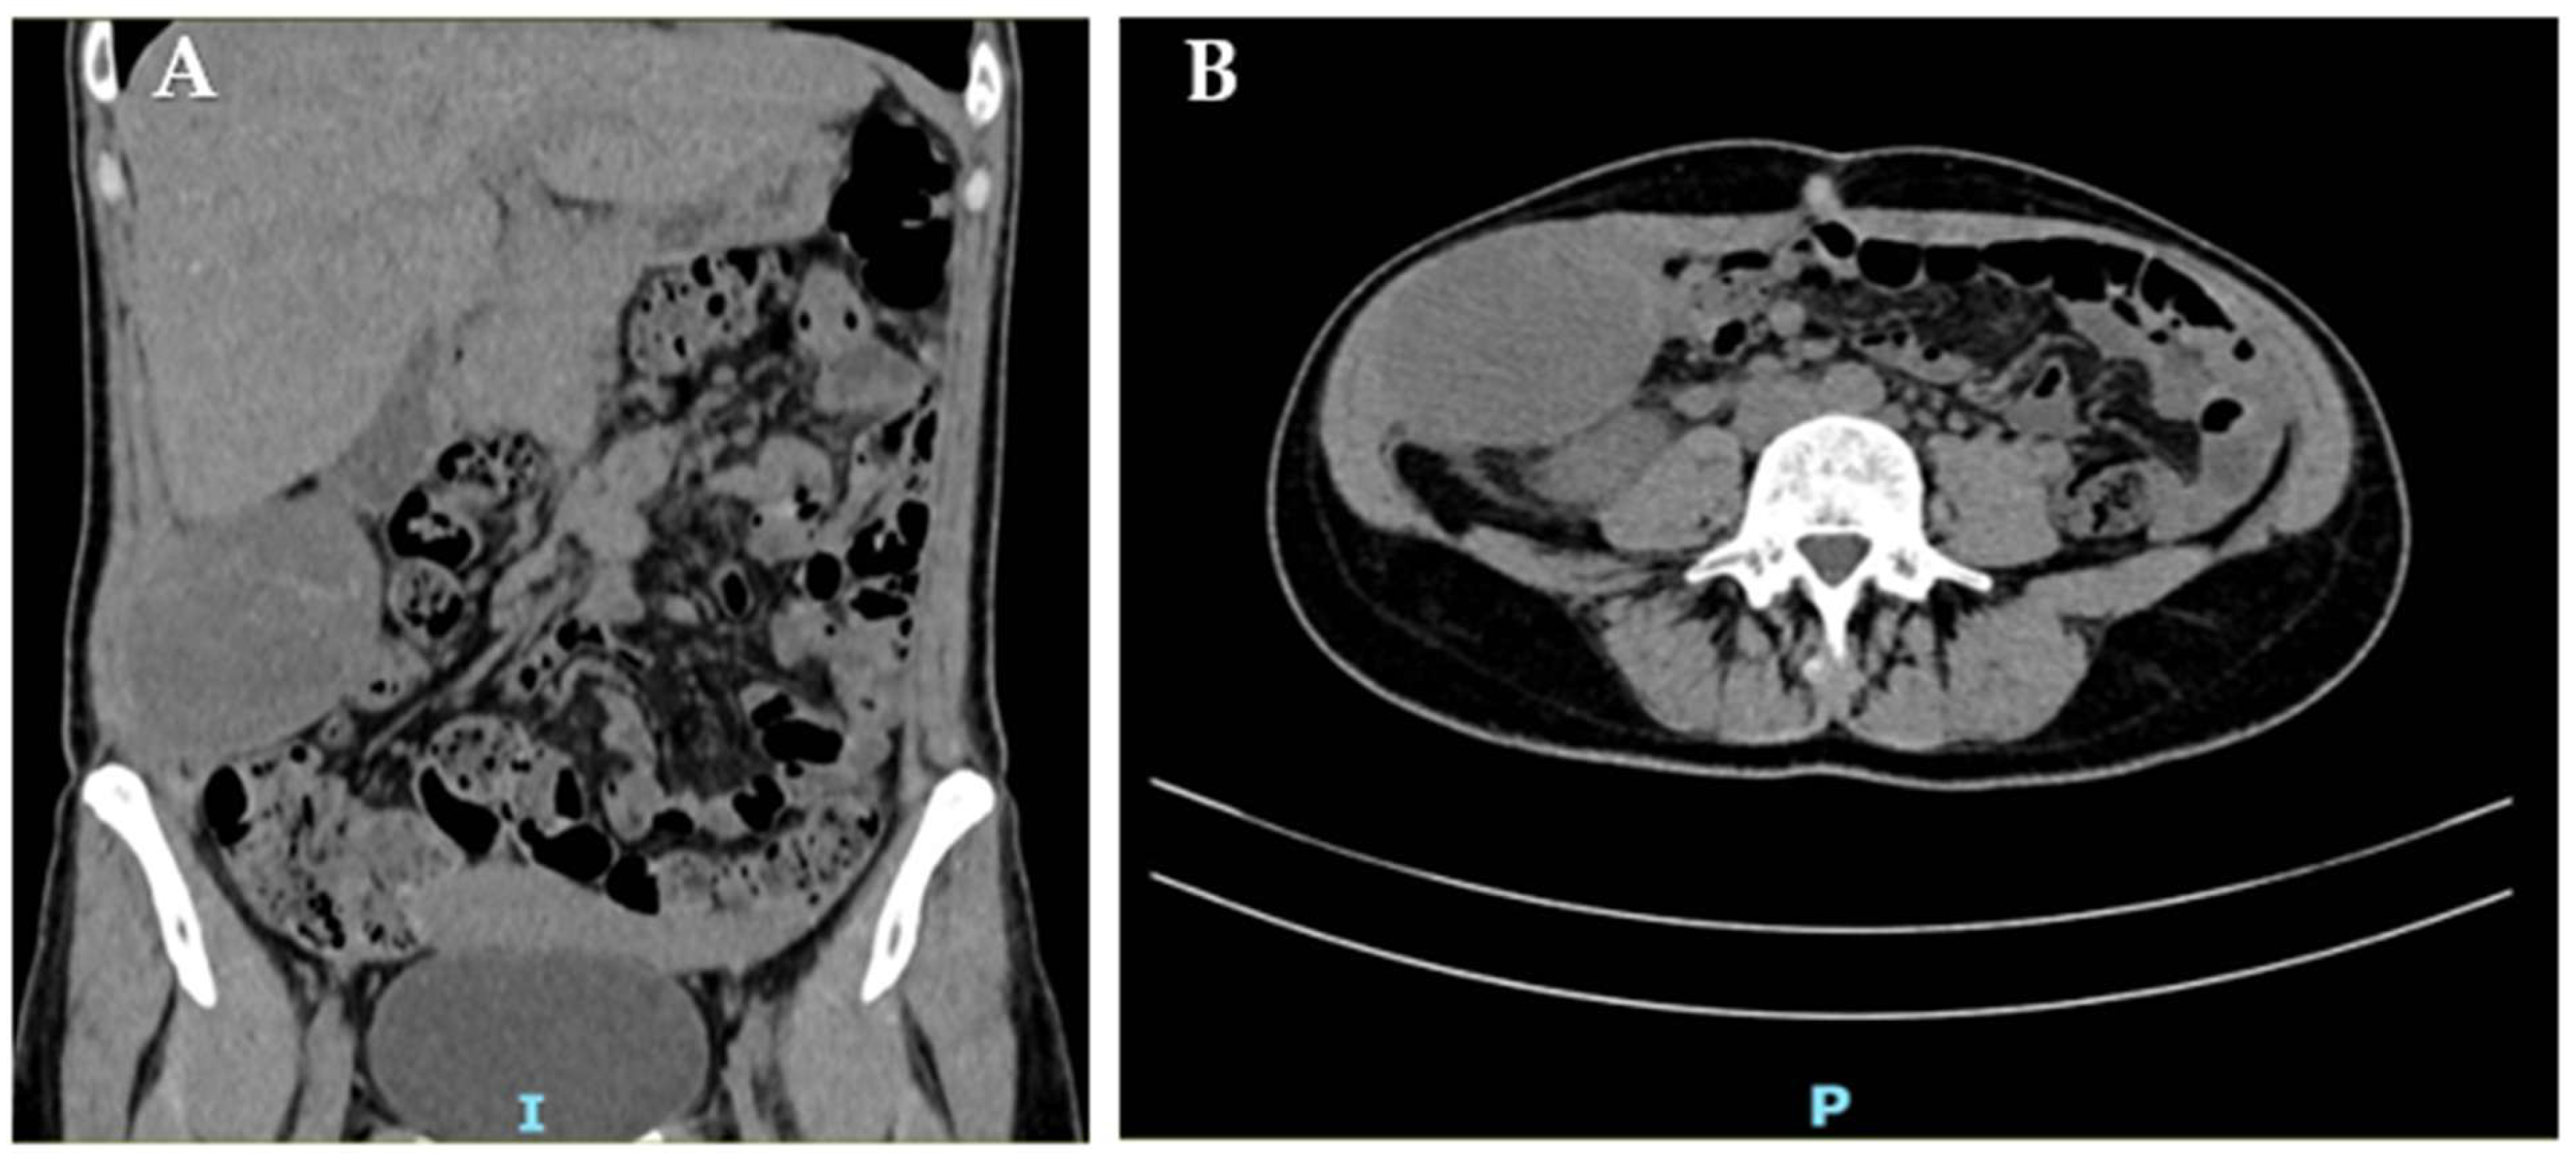

Two months post-partum, CT undertaken elsewhere for febrile pyelonephritis demonstrated marked enlargement of the known abdominal-wall lesion to 70 × 50 × 93 mm, displacing but not invading the right kidney (Figure 2).

Figure 2.

CT scan of the right abdominal wall: coronal (A) and axial (B) view of the abdominal-wall DT.

The mass remained heterogeneous and predominantly hypodense with peripheral enhancement, and it was again interpreted as an endometrioma; residual splenosis nodules persisted (largest 3.3 cm).